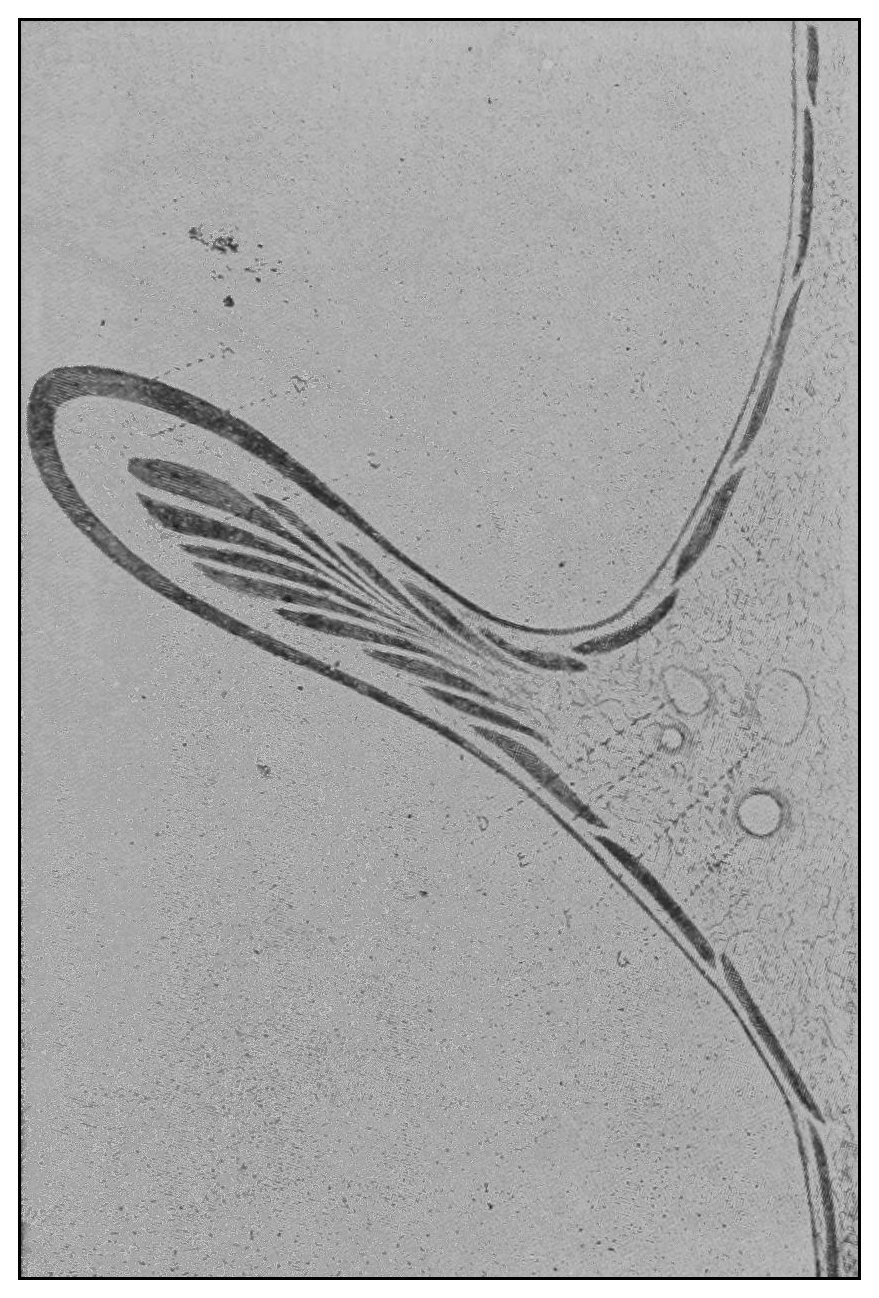

The photographic reproductions here published are documentary evidence of the existence of the obstructions under discussion. The sketch, Fig. 33, which was drawn from the valve while under the microscopic lens, exhibits the character of these obstructions and proves it that of a typic anatomic valve, and the absence of permanent bands of any other character in this organ is evidence that the semilunar valves and the so-called plica transversalis recti, Falten des Rectums, sphincter ani tertius, superior sphincter, and detrusor fecium muscles are one and the same thing and this thing is essentially a valve. It is most prominent when the gut is most distended.